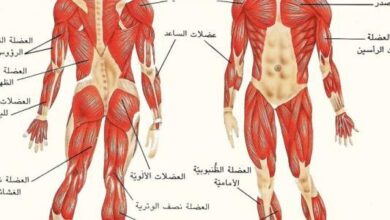

يحتاج الجسم لمادةٍ ناقلة تكون حلقة وصل بين المواد المُراد نقلها والأعضاء والخلايا المختلفة؛ حيث يؤدّي هذه الوظيفة المهمة الجهاز الدوراني في جسم الإنسان وهي شبكة واسعة من الأعضاء والأوعية الدموية، وهي مسؤولة عن تدفق الدم في جميع أجزاء الجِسم.

يُعتبر سريان الدم في أنسجة جسم الإنسان ذا أهميّةٍ كبيرةٍ لبَقاء جَميع الأعضاء حيّة، حيث أنها تنقل الأكسجين والهرمونات والغذاء والغازات الأخرى من وإلى الخلايا، ومن دون هذا الجهاز فإنّ الجسم يكون غير قادرٍ على مُحاربة الأمراض أو الحفاظ على استقرار الحرارة والحموضة والبيئة الداخلية للجسم.[٢]

يحتوي جهاز الدوران على أجزاء مهمة تُعتَبر من أهمّ الأجزاء الوظيفية في جسم الإنسان، وهي:[٥]

- الشرايين.

- الأوردة.

- القلب.

- الشعيرات الدموية.

- الرئة.

- الكليتين.